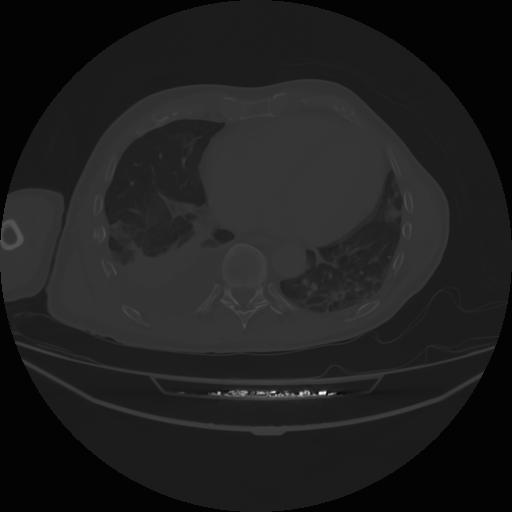

4 CUERPO,CE,Axial,3.0,CUERPO,,